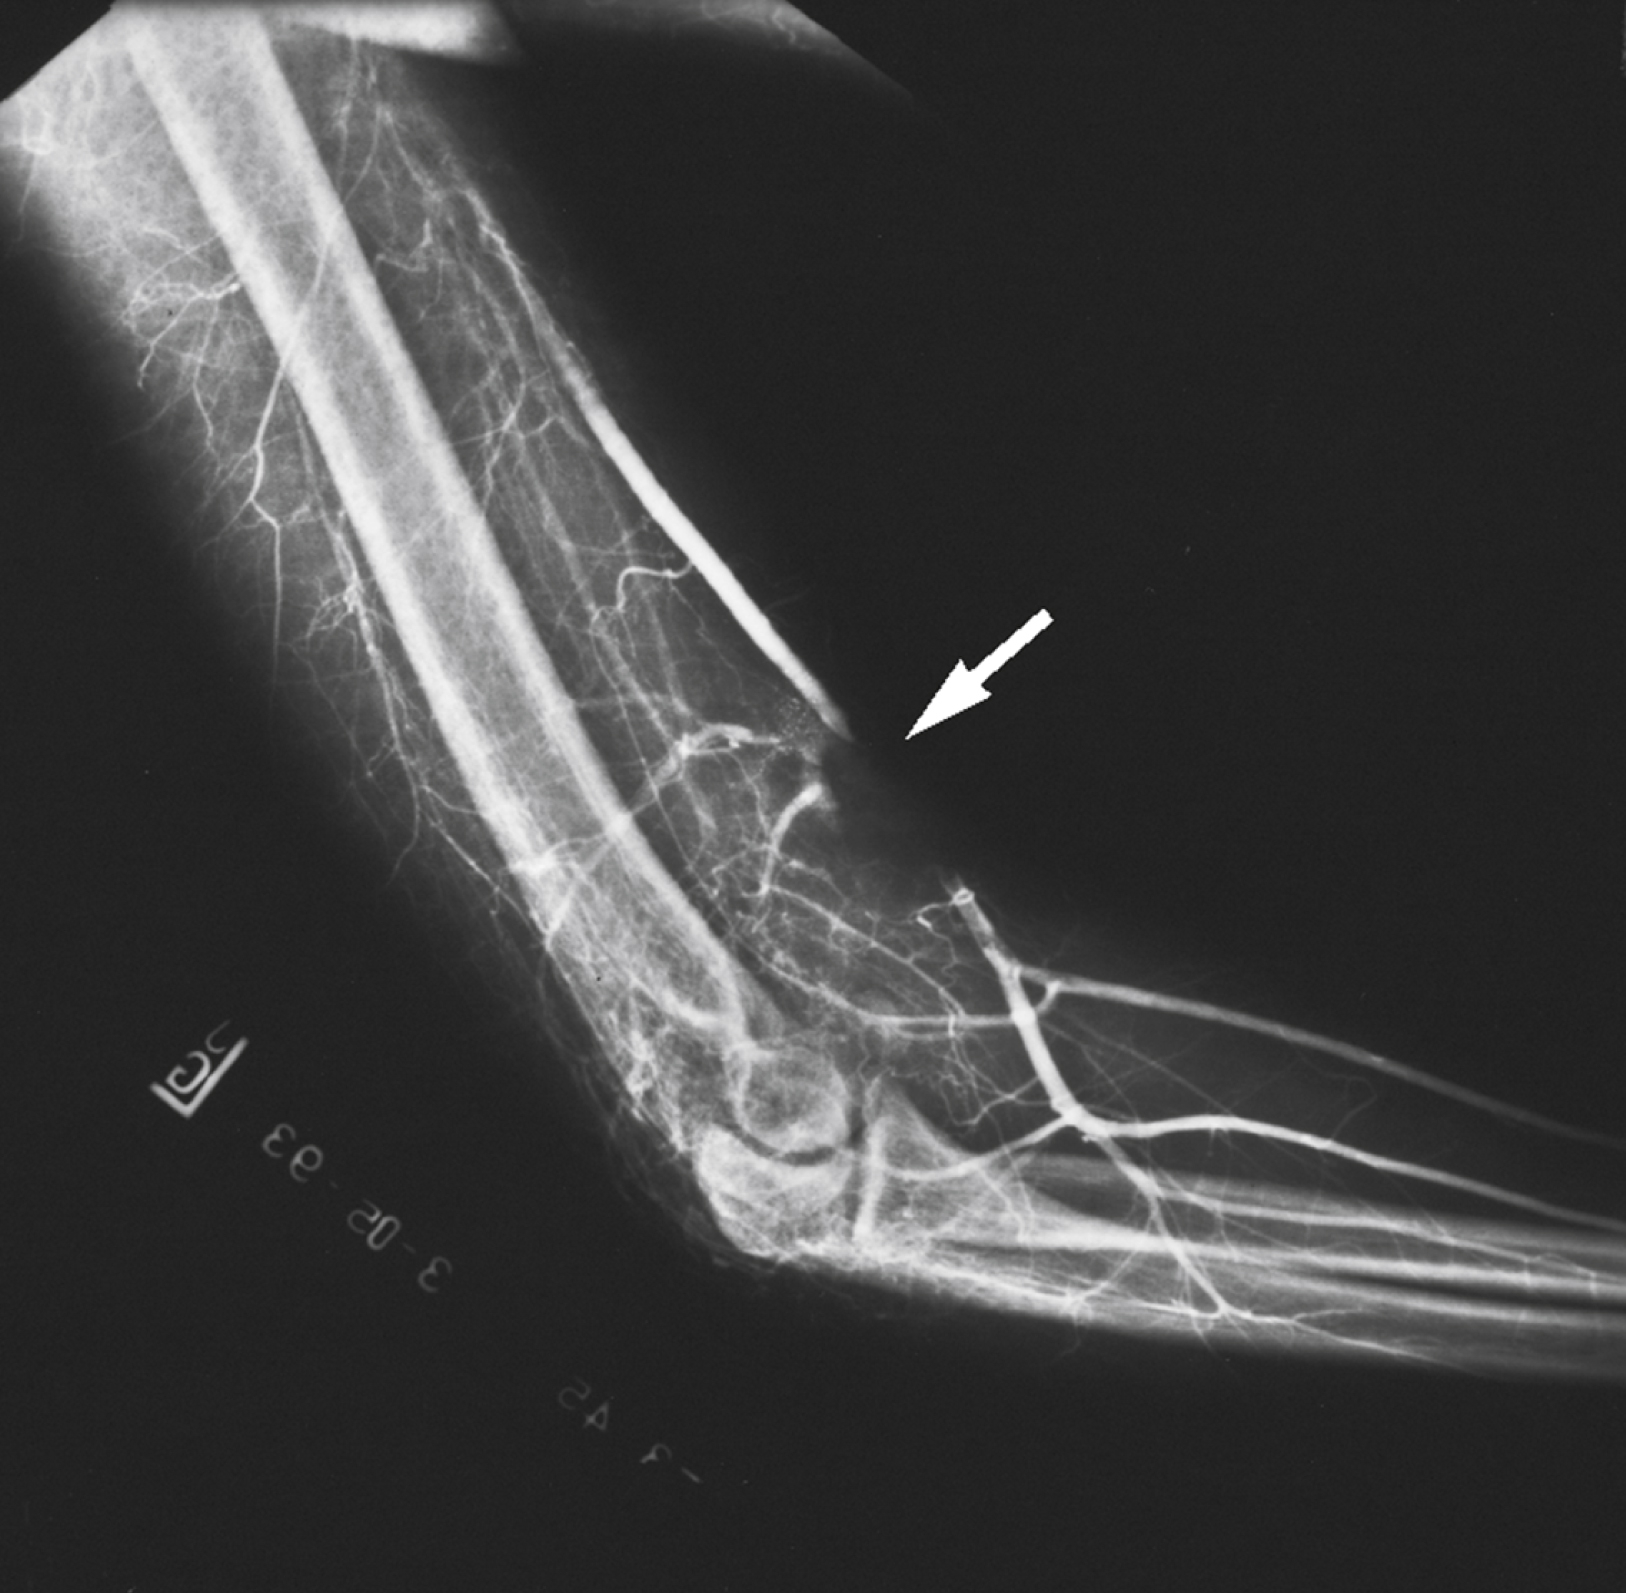

Reversible arterial spasm

The precise cause and incidence of significant reversible arterial spasm after trauma are unknown. In the case of arterial transection, arterial spasm is beneficial and limits hemorrhage. However, in other cases, the segmental arterial spasm occurs at some distance from the site of traumatic injury and can produce severe distal ischemia. Arterial spasm is particularly common in children. In many series, segmental arterial spasm is the most common arteriographic finding ( Fig. 40.4 ). However, symptoms of ischemia should not be assumed to be a result of arterial spasm; that diagnosis is based on arteriographic results only.

Acute Arterial Spam of the Brachial Artery.

From Arquilla B, Gupta R, Gernshiemer J, et al: Acute arterial spasm in an extremity caused by inadvertent intra-arterial injection successfully treated in the emergency department. J Emerg Med 2000;19[2]:139–143.